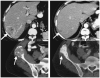

Figures